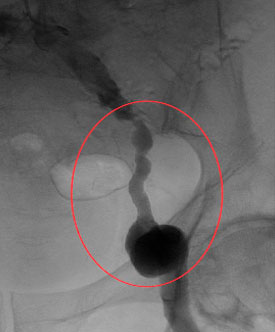

В отделении ССХ клиники ЦЭЛТ выполнена ангиография нижних конечностей

Обследование в отделении сердечно сосудистой хирургии подтвердило сложное, многоуровневое поражение артерий левой нижней конечности: аневризма наружной подвздошной и общей бедренной артерий, закупорки и сужения были обнаружены на всем протяжении – от подвздошных артерий в малом тазу до мелких сосудов голени. Кровоток до стопы доходил в малом количестве, через обходные пути (коллатерали).

Значимый стеноз общей подвздошной артерии, аневризматически расширенная наружная подвздошная артерия |

Аневризматичски расширенная общая бедренная артерия, окклюзия поверхностной и глубокой бедренной артерий |